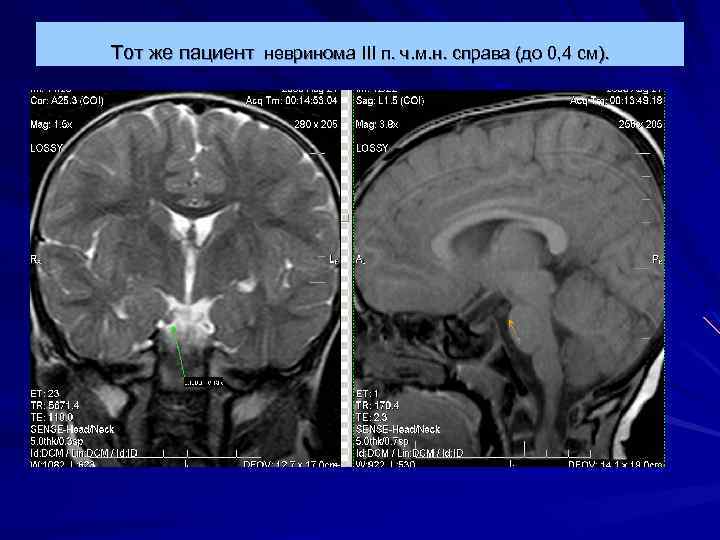

Тот же пациент невринома III п. ч. м. н. справа (до 0, 4 см).